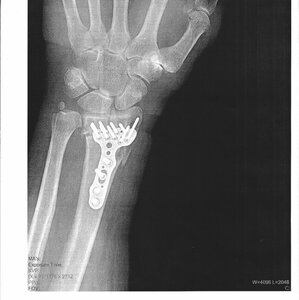

I had an accident up snowboarding yesterday. By the time I got home my ankle was swelling fast. the wife ran me down to the ortho clinic and sure enough i broke my leg - maybe in two places - on break is certain. Booted now, surgery Wednesday. getting some new titanium implants put in to hold everything it the right places. I think the doc said no weight bearing for at least 6 weeks. gonna miss wo month of the season, cooking is almost out of the question.

In an odd twist of fate - I had the same break on the same leg about 25 years ago. that one was much worse, it was super displaced and almost a compound fracture. spend 4 days in the hospital that time. this one is out patient and Im hoping they have better methods. the first surgery was the most pain i have ever felt.

I was having fun when I broke my right tib/fib back in '04.

Xray%20plates%20and%20screws%202002.jpg